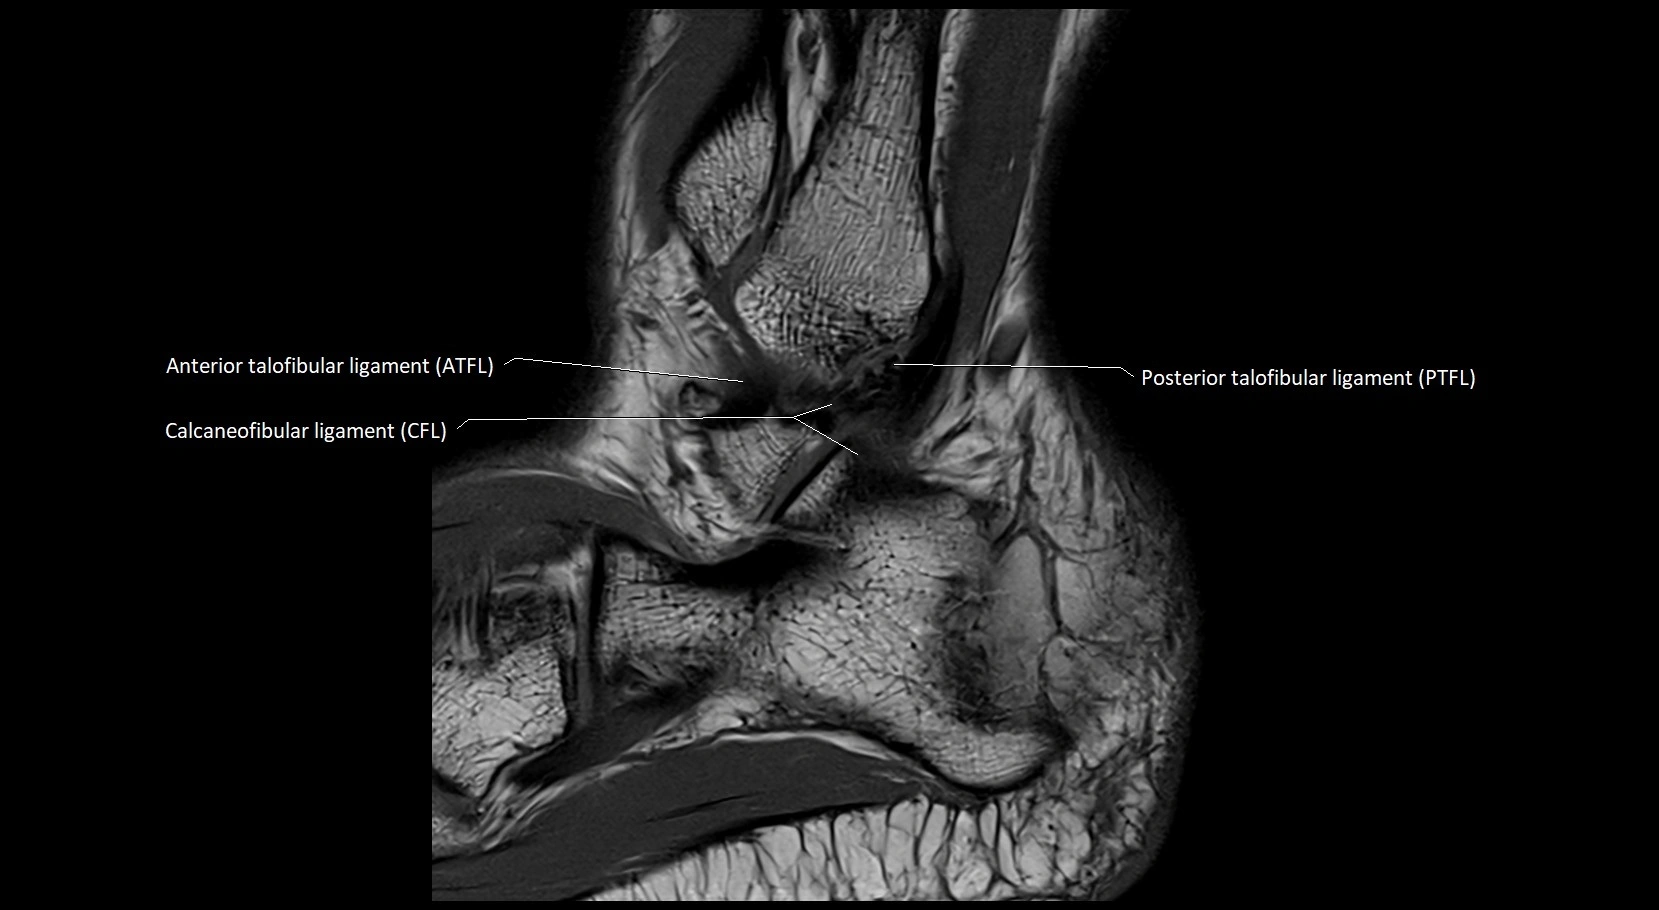

MRI image

image